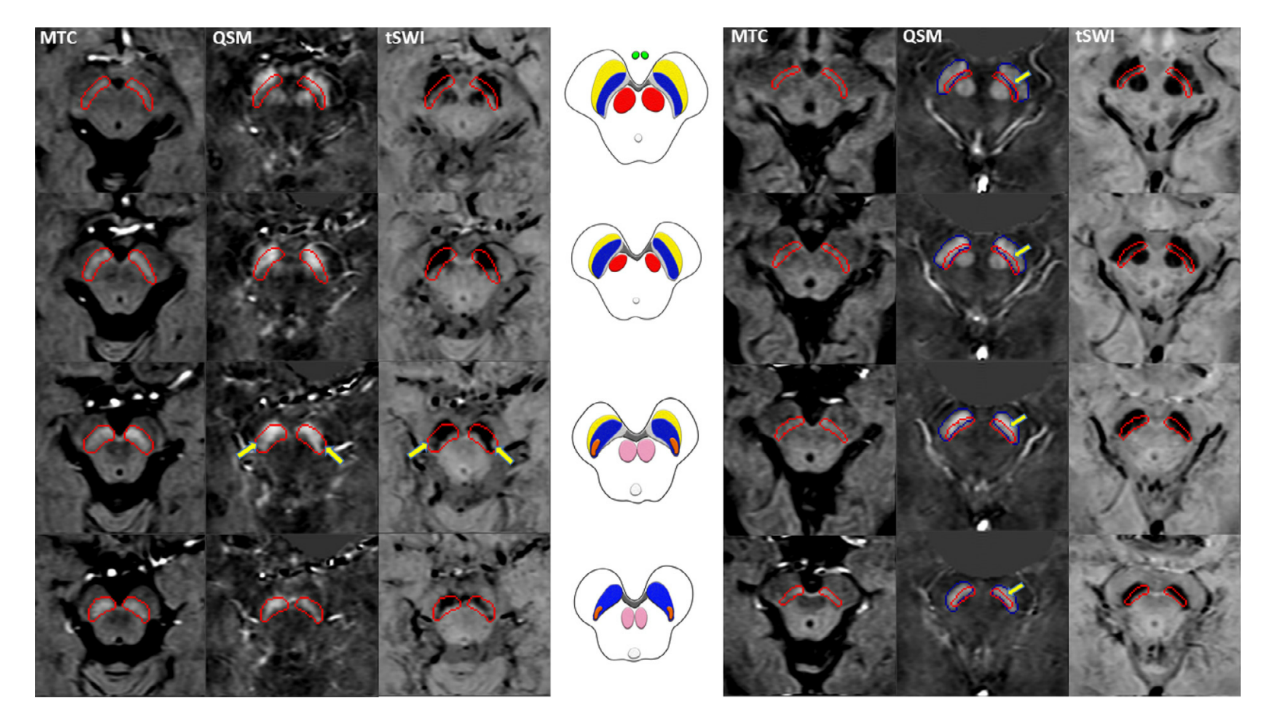

neuroimage磁共振3d梯度回波磁化转移序列同时对铁和神经黑色素进行

图片尺寸1270x714